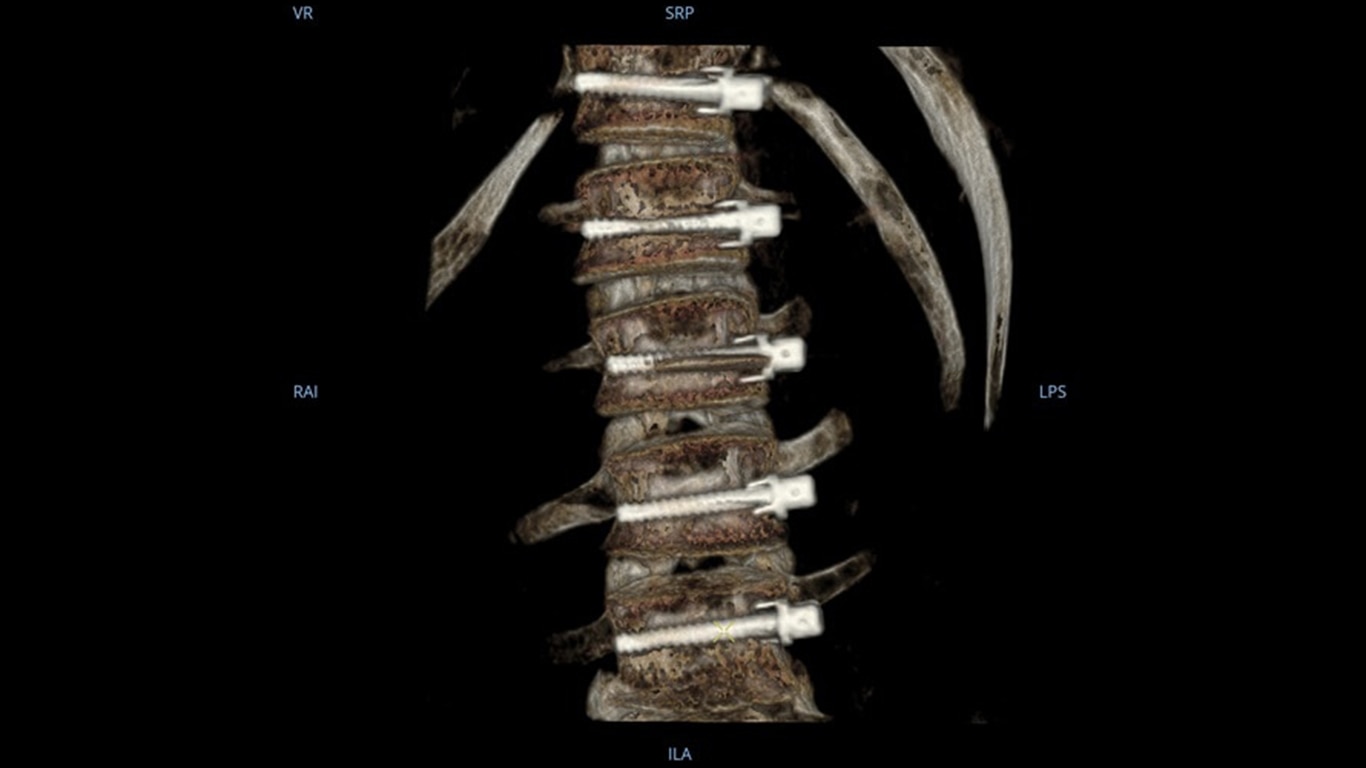

Mehr sehen, schneller entscheiden: Der OEC 3D ermöglicht die gleichzeitige Darstellung mehrerer Ebenen bei verschiedensten Anwendungen. Ob Spondylodesen, komplexe Trauma- Chirurgie oder Bronchoskopien. Mit einem Volumen von 19 × 19 × 19 cm liefert er bis zu 67 % mehr Bildinformationen als vergleichbare Systeme – für mehr Sicherheit und Effizienz im OP.

Analysieren Sie Ihre Scans mit dem GE Volume Viewer – genauso intuitiv wie am CT. Profitieren Sie von der vollständigen Darstellung axialer, koronarer und sagittaler Ebenen sowie von MIP-Ansichten und 3D-Visualisierungen im VR-Modus. Scrollen Sie durch bis zu 512 Schichten mit nahtloser Anpassung der Schichtdicke – für eine präzise Befundung direkt im OP.